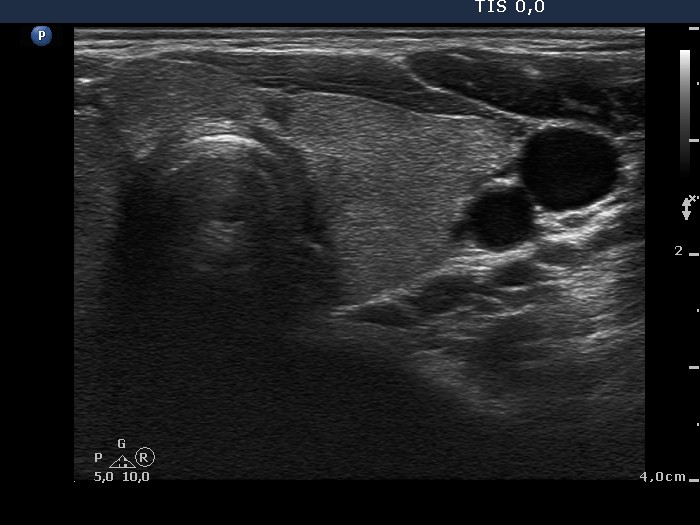

Graves' disease - Case 1049

Follow-up investigation 40 months after first visit (ultrasonographic picture 4)

Patient on daily 5 mg methimazole therapy in hypothyroid state

Left lobe, transverse view. The thyroid is intact.